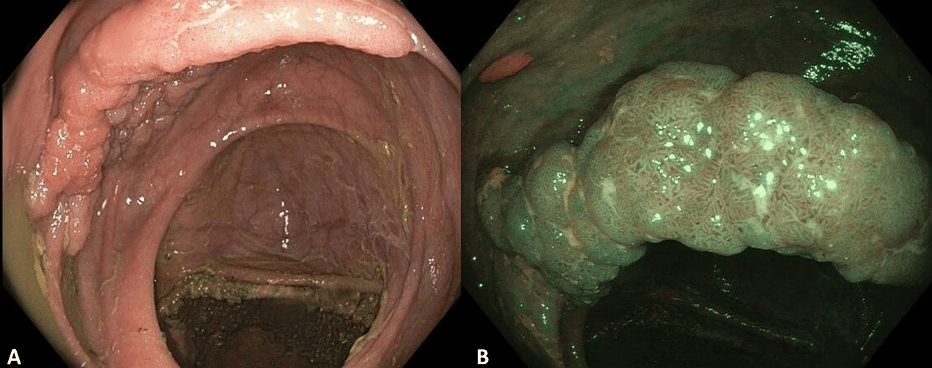

Quick Case: Laterally Spreading Tumor LST in Ascending Colon

Laterally spreading tumors (LSTs) are defined as nonpolypoid lesions ≥1 cm with lateral growth.

The two main categories of LST, based on their surface morphology, are granular (G) and non-granular (NG).